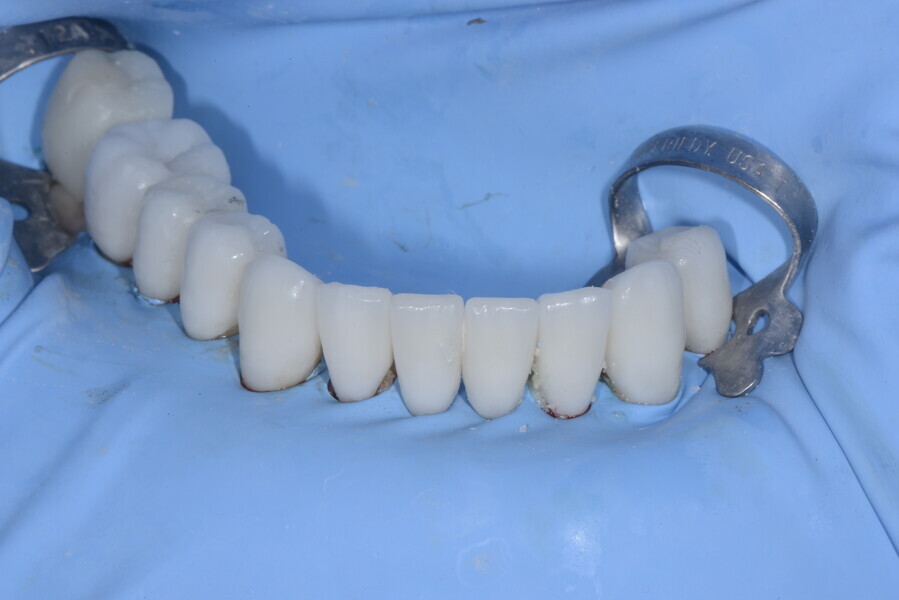

After the first phase of aligner treatment, we had achieved better inter-arch coherence, better maxillary arch expansion, and some space for improving the anterior tooth proportions restoratively (Fig. 19). We then temporarily restored the anterior teeth directly with composite, closing the spaces, improving the tooth proportions and further increasing the maxillary arch expansion (Fig. 20). We used restorative arch expansion to reduce the orthodontic destabilisation of the teeth to achieve the correct inter-arch coherence and retain the teeth in the cortical bone.38 A refinement aligner phase was undertaken to improve the final alignment of the gingival zenith and to improve the inter-arch coherence (Fig. 21). The periods of the first orthodontic phase and of the refinement were used to augment the mandibular and maxillary bone and to place the implants (Fig. 22). At the end of the orthodontic treatment, the case was finalised with ceramic veneers in the anterior area and temporary restorations on the implants in the posterior area (Figs. 23–26).

The provisional phase of about four months was important to allow the peri-implant tissue to mature and to teach the patient to chew correctly with chewing gum, cotton rolls and silicone masticatory sticks. This is fundamental training for the patient to achieve the correct alternating unilateral masticatory cycle needed to obtain the ideal rehabilitation of the masticatory system. We wanted the patient to achieve ideal masticatory and swallowing function. After sufficient rehabilitation time, we finalised the case with posterior zirconia crowns screwed on to the implants (Fig. 27).26